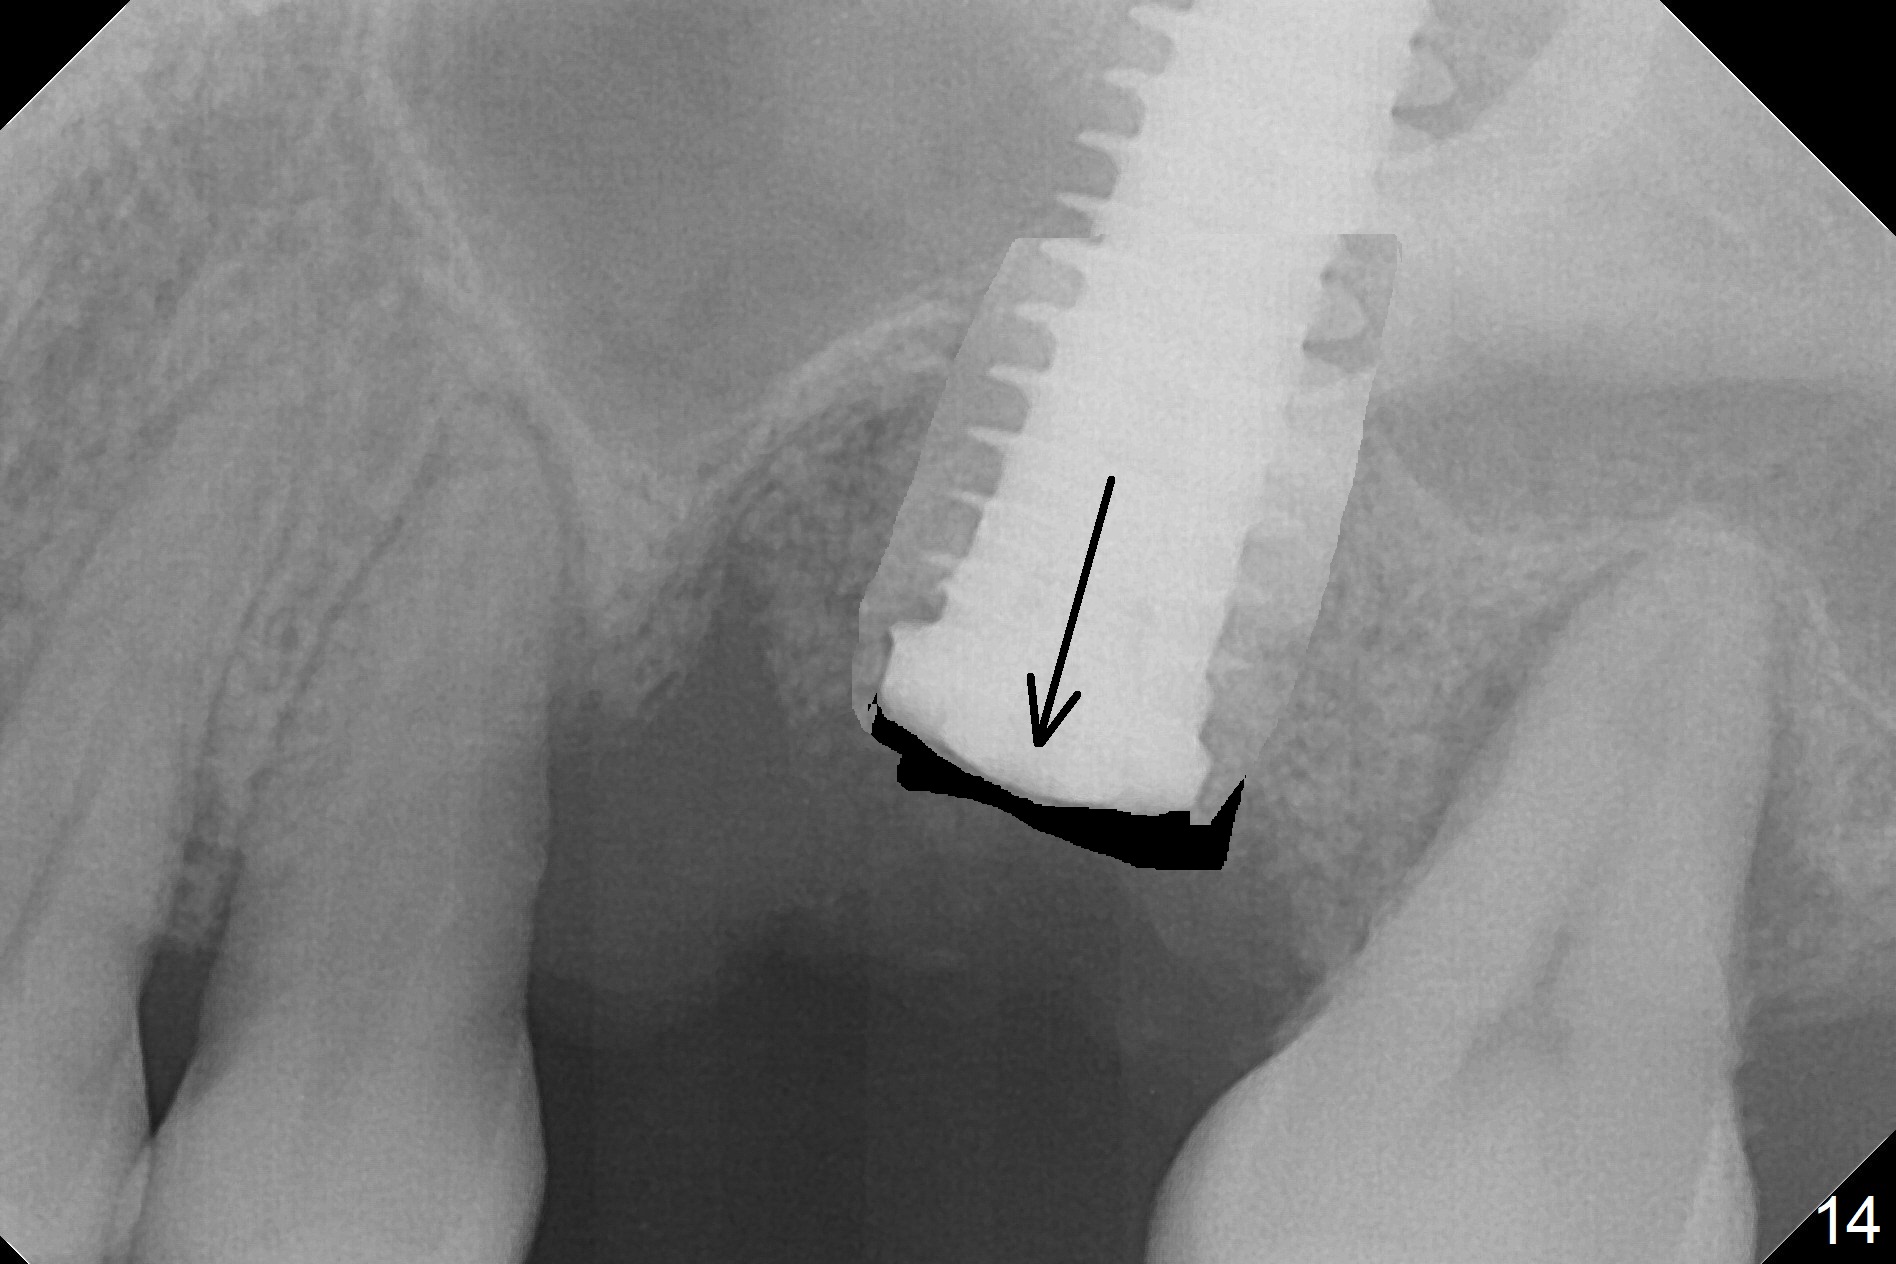

Questions for Dr. Wang: Can we remove the coronal portion of the bone (Fig.13) and back up the implant (Fig.14 arrow) 4-5 months postop for easy restoration?  If it is not a good option, can we produce pair abutments with 5 and 7 mm cuffs?

Poor visibility for immediate implant in the molar region is another contributing factor for the dislodgement.  The patient returns for follow up 15 days (Fig.15) and 1 month (Fig.16) postop.  Bone graft seems to be stable around the implant.  The socket heals 4 months postop (Fig.20).  The implant seems to have been osteointegrated (Fig.17,18).  It will be backed up for ~ 3 mm to improve implant/crown ratio (Fig.19, as compared to Fig.14).  If it cannot be done, take impression immediately and make a subgingival provisional before suturing.